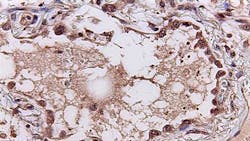

Two telltale signatures emerged from the study, published in eBiomedicine. One, a set of 166 genes, reveals how the human immune system responds to viral infections. A second set of 20 signature genes predicts the severity of a patient’s disease. For example, the need to hospitalize or use a mechanical ventilator. The algorithm’s utility was validated using lung tissues collected at autopsies from deceased patients with COVID-19 and animal models of the infection.

By examining the source and function of those genes in the first signature gene set, the study also revealed the source of cytokine storms: the cells lining lung airways and white blood cells known as macrophages and T cells. In addition, the results illuminated the consequences of the storm: damage to those same lung airway cells and natural killer cells, a specialized immune cell that kills virus-infected cells.